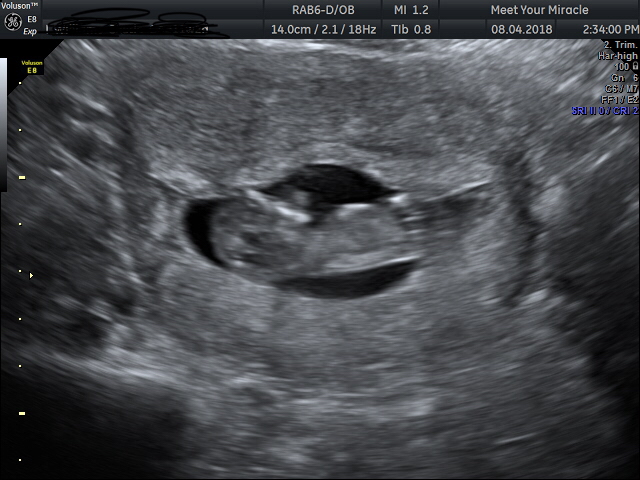

This is our 4th child, please can anyone have a look to see if there is any hints to the gender of our last baby. we have 2 Son’s & a daughter already. Thank you so much Attachment 39318

Do you know gestation on this? Baby looks too early for me to think nub theory would work.

Hi yes the gestation was 11+2 x